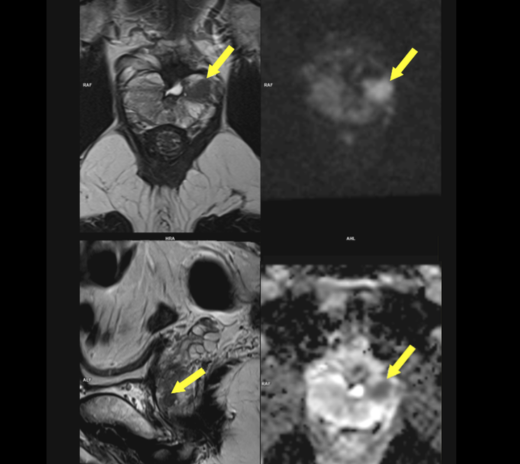

磁力共振扫描影像(前列腺)